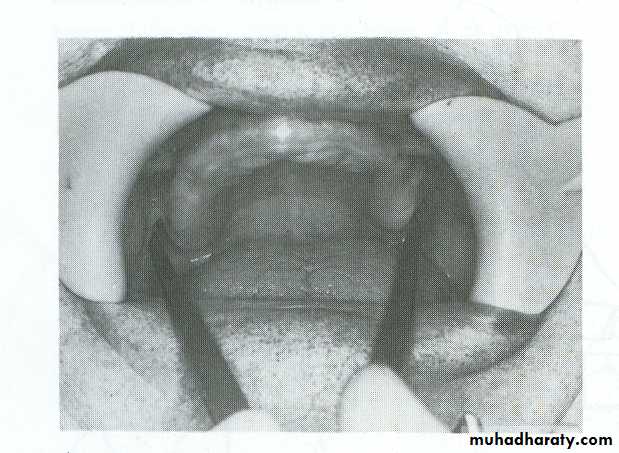

The negative likeness of the oral tissues made for the prepare of diagnosis, treatment planning, or the fabrication of tray. It’s the first impression made for the patient and from which the study cast was produced. This impression is obtained by stock tray.For upper stock tray, the posterior border of the tray should cover the maxillary tuberosity and hamular notch, anteriorly should include the antero-alveolar ridge

For lower stock tray posteriorly should cover the whole area of retromolar pad area and anteriorly include the alveolar ridge